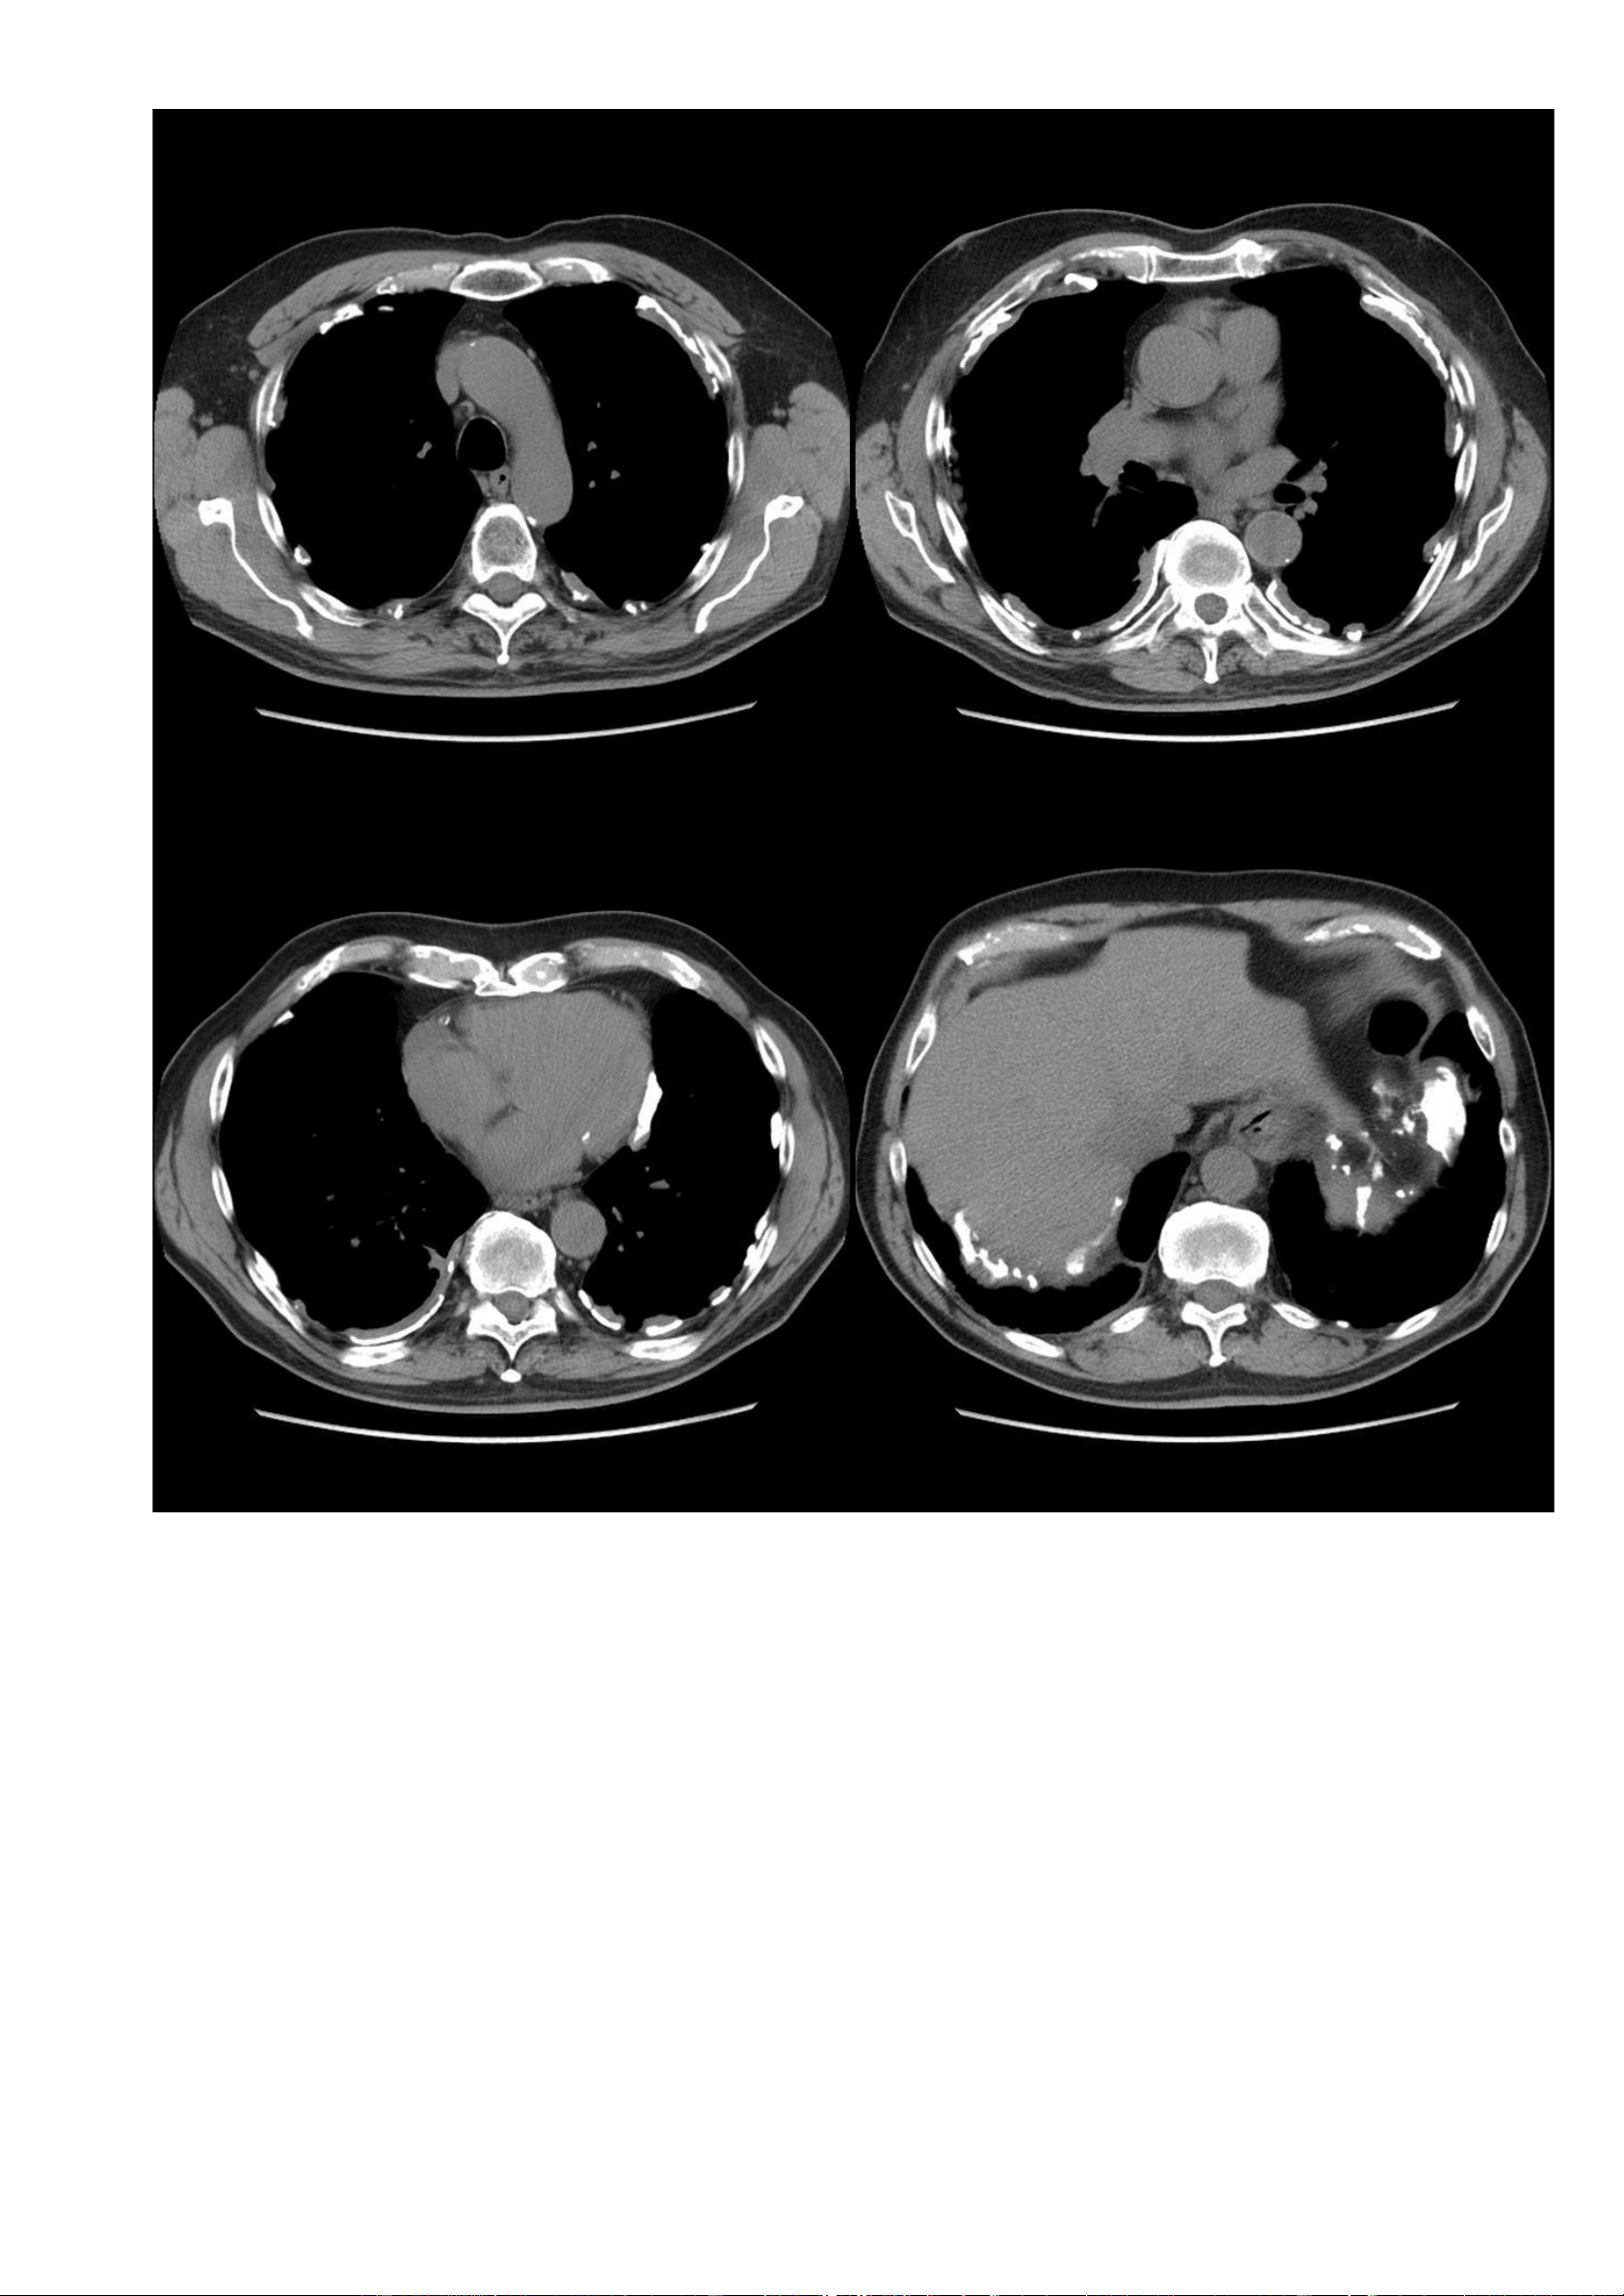

Hình ảnh CT (cửa sổ trung thất – thì tĩnh mạch cửa): lOMoAR cPSD| 22014077 Phan Tùng Bách

Các mảng màng phổi vôi hoá. lOMoAR cPSD| 22014077 Phan Tùng Bách ờng hợ n link: Thông tin bệ nh X quang: 7.4. Trư p 4: -